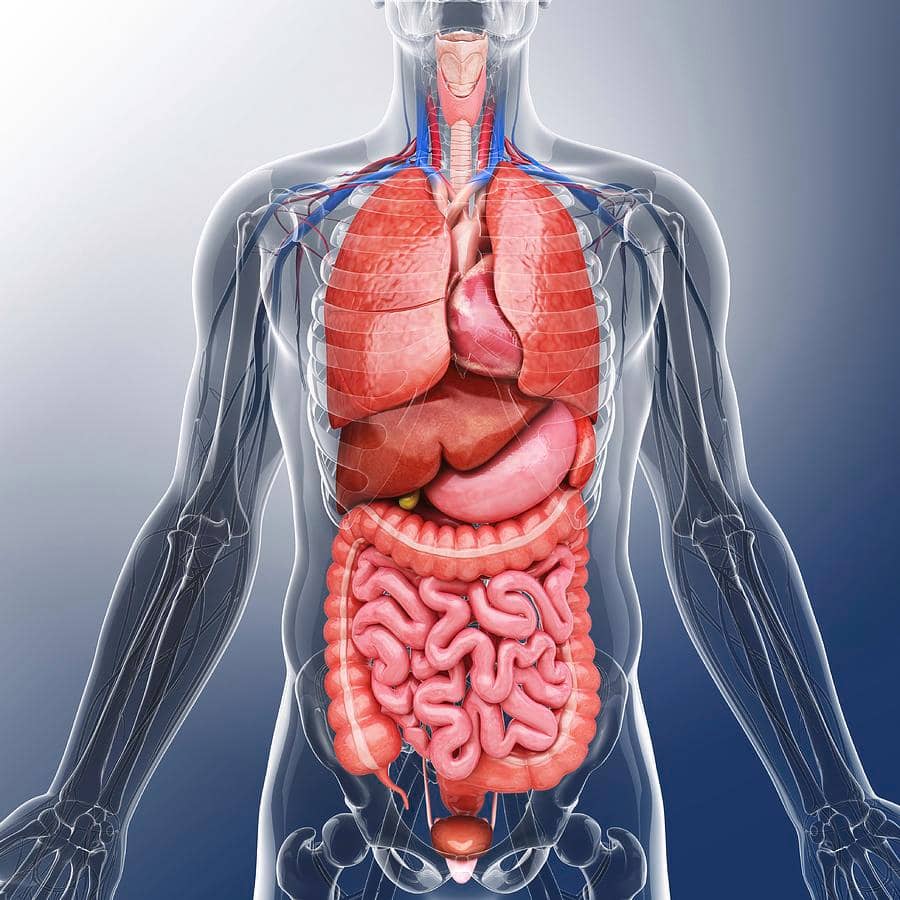

Изображения и визуализация внутренних органов человека